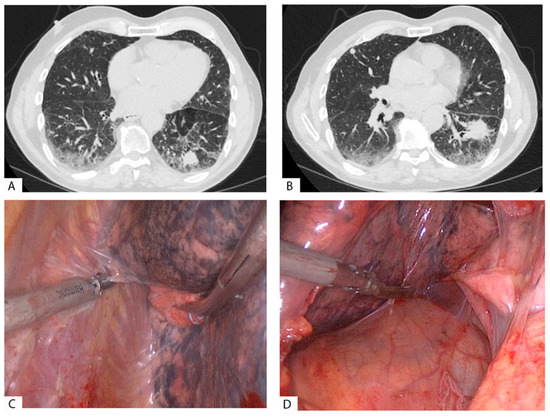

We reported two cases of extensive pleural adhesions in patients with a history of COVID-19 in Figure 1 and Figure 2; in both cases, the surgery was carried out using a thoracoscopy.

Figure 2.

Patient with squamous adenocarcinoma in the right lower lobe (RLL) treated with VATS in the right lower lobectomy. (A,B): Thoracoscopic view and dissection of pleural adhesions in the parietal pleura of the RLL. The adhesions were firm and vascular, localized in a portion of the pleural cavity.